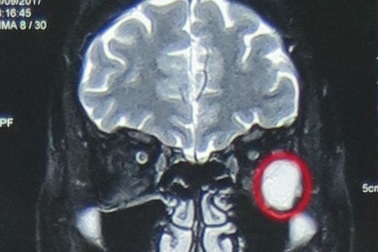

u hốc mắt trái